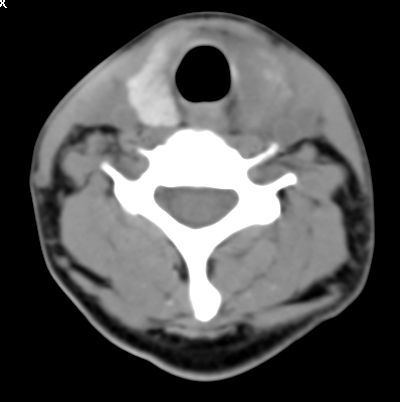

标题: CT9717:F、30Y、颈部左侧包块半年,压痛.患者拒绝作增强。 [打印本页]

标题: CT9717:F、30Y、颈部左侧包块半年,压痛.患者拒绝作增强。

请各位老师帮忙看看左侧甲状腺病灶!

左侧甲状腺见一低密度灶,考虑甲状腺占位。(腺瘤?)

甲状腺弥漫增大,以左叶明显,内见不均匀低密度影,边缘模糊欠清,周围脂肪间隙模糊。

结合病史:考虑亚急性甲状腺炎可能性大。(不知道病人有没有检测tsh t3 t4)

左侧甲状腺及甲状腺狭部弥漫性增大,边缘模糊,未见明确界线.考虑甲状腺炎可能性大.

甲状腺弥漫增大,以左叶明显,左侧内见不均匀低密度影,边缘模糊欠清,周围脂肪间隙模糊。